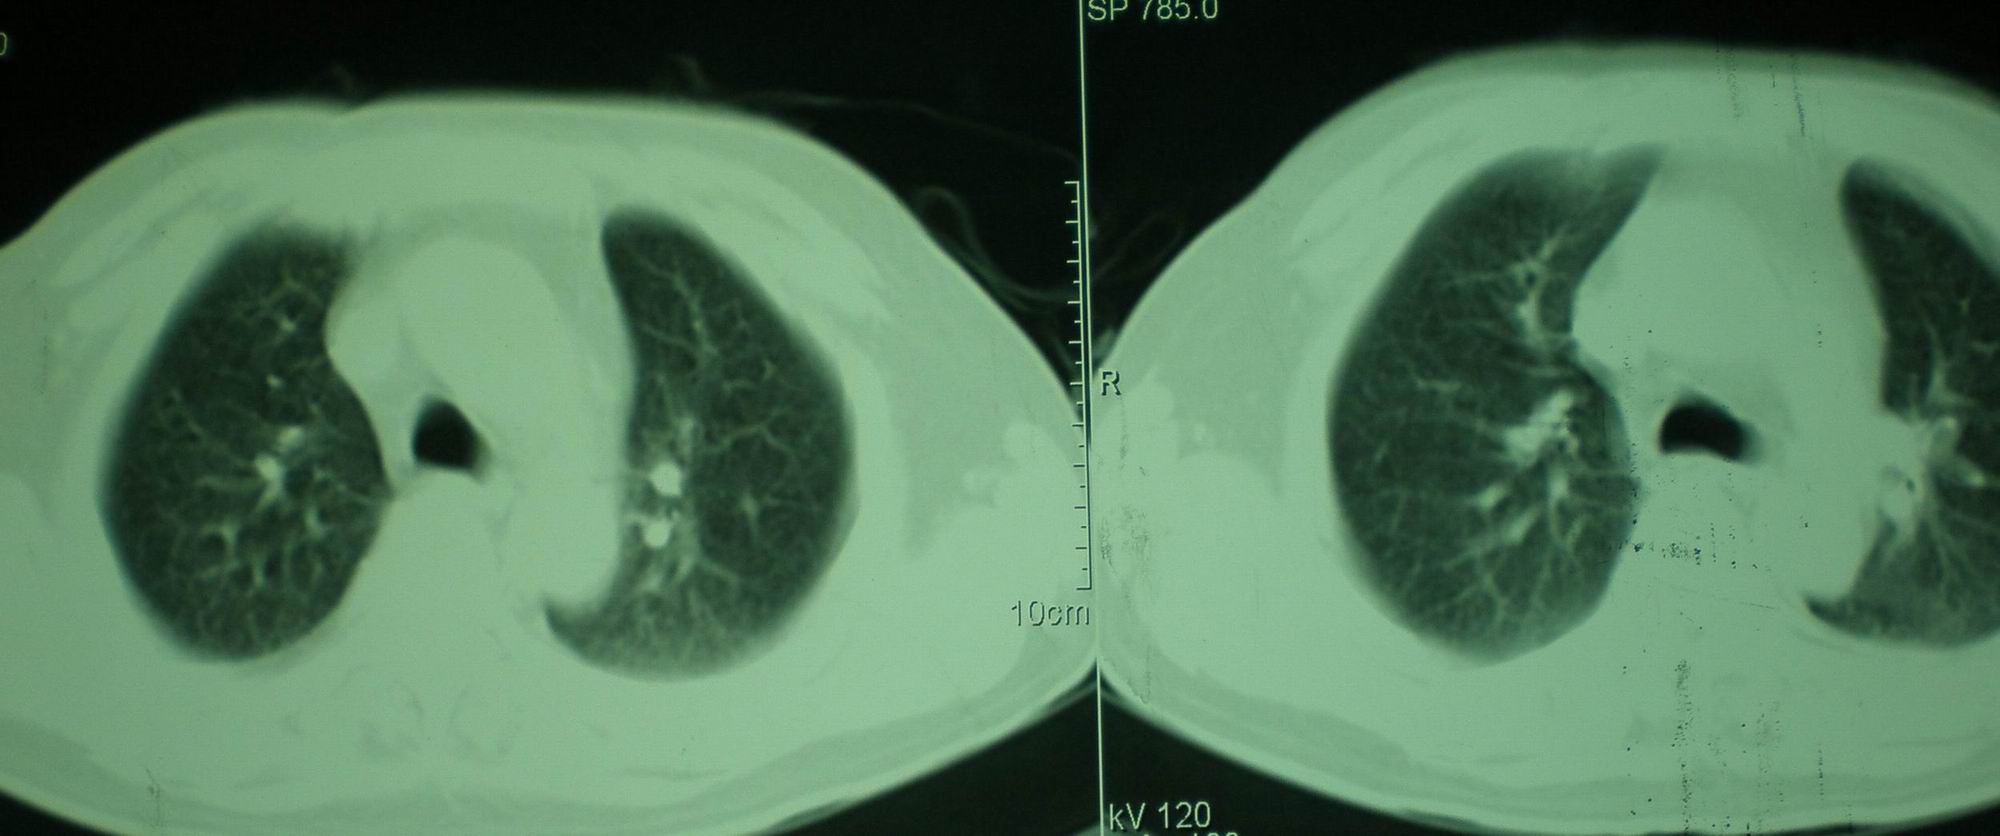

2008年9月18日ct片

[face=宋体]显然上级医院进行了抗结核,抗真菌,抗炎等治疗,目前病人肺内病灶基本消失,双侧胸腔积液,右侧积液量有吸收,抗结核一个多月,现在病人疑问,结核的诊断是否有疑义,抗结核是否继续,因为那个毕竟副作用大。[/face]

我仔细看了下病人的出院小结,当时情况危急,诊断里有1型呼衰。心包周围的是脂肪密度。结合三次ct扫描的图象分析,个人认为:1、病人目前肺部病灶基本消失,双侧胸腔内少量积液,抗结核治疗才一个多月,就算是结核,抗结核治疗有效果,为何效果如此好,一点纤维灶的痕迹都没有呢,再就是患者做过气管镜检查及活检、痰检均未找到结核的证据。所以不支持结核的诊断。

2、结合现在的ct片,考虑:肺水肿及真菌感染,双侧胸腔积液。

机遇性感染。双肺实质满布。且以肺门周围为主。不象结核。